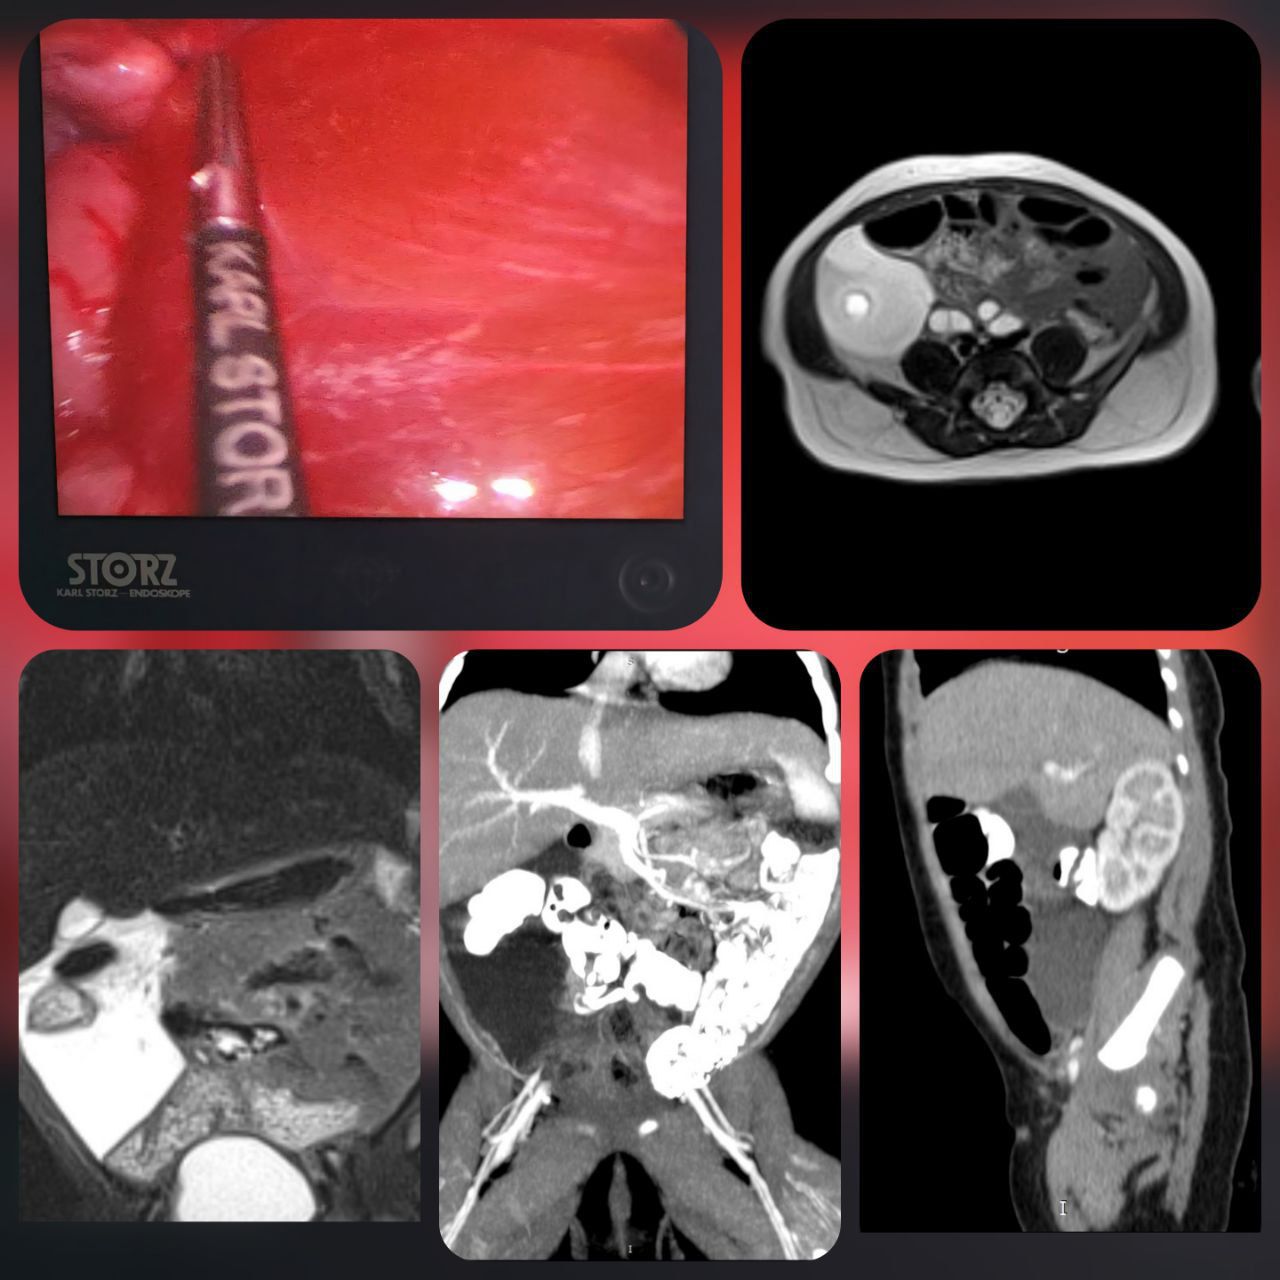

Специалисты отделения хирургии детей раннего возраста провели комплексное обследование, включая МРТ брюшной полости, подтвердившее редкую аномалию развития лимфатических сосудов в брыжейке толстой кишки.

Хирурги ХДРВ – заведующая отделением, к.м.н. Зыкова Мария и врач-детский хирург Буй Вьет Анх выполнили малоинвазивную операцию – лапароскопическое удаление лимфатической мальформации, сохранив при этом сосуды брыжейки толстого кишечника. Для предотвращения повторного появления заболевания внутренняя поверхность лимфатических кист была обработана «Лимфоблоком» – специальным раствором, формирующим полимерное покрытие, препятствующее образованию лимфы.

Описанный случай локализации лимфатической мальформации в брыжейке толстого кишечника является крайне редким. Чаще всего подобные образования обнаруживаются в области шеи и подмышечных впадин. Такие поражения составляют менее 1% всех лимфатических мальформаций.